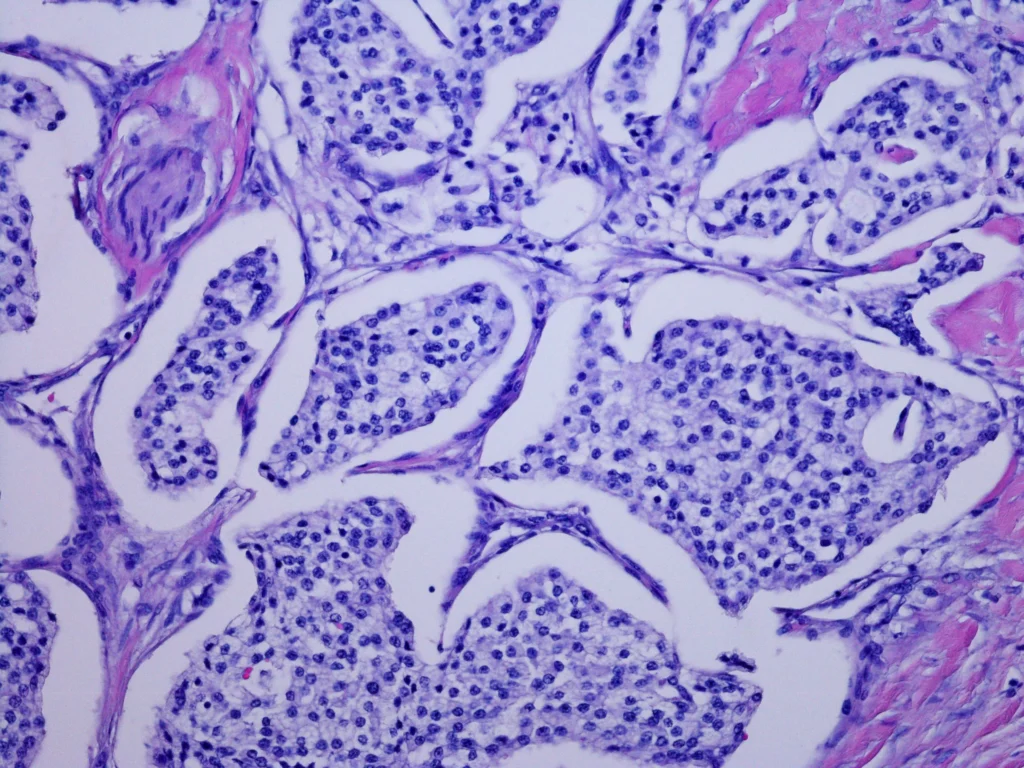

Los tumores neuroendocrinos del tracto gastrointestinal y del páncreas (GEP-NETs) son neoplasias que se originan en las células neuroendocrinas ubicadas en los tejidos del estómago, los intestinos o el páncreas endocrino. Estas células tienen la capacidad de producir hormonas que son esenciales para la regulación de diversas funciones corporales. Los GEP-NETs son un grupo heterogéneo de neoplasias, que se caracterizan por una amplia variedad de tipos funcionales y no funcionales, y que se presentan en diversos lugares del sistema gastrointestinal y endocrino.

Además de los tumores pancreáticos, los tumores carcinoides, que son una forma de GEP-NET, pueden surgir en diferentes áreas del tracto gastrointestinal, como el intestino delgado, el colon, el esófago, el estómago o incluso los pulmones. Los tumores carcinoides del intestino delgado, especialmente en la región del íleon terminal, son los más comunes. Aunque estos tumores suelen tener un curso indolente, son propensos a la metastasis, especialmente al hígado, los ganglios linfáticos y el peritoneo. En alrededor del 20% de los casos, la metástasis está presente sin una localización primaria conocida. En aproximadamente el 28% de los casos, los tumores carcinoides son múltiples.